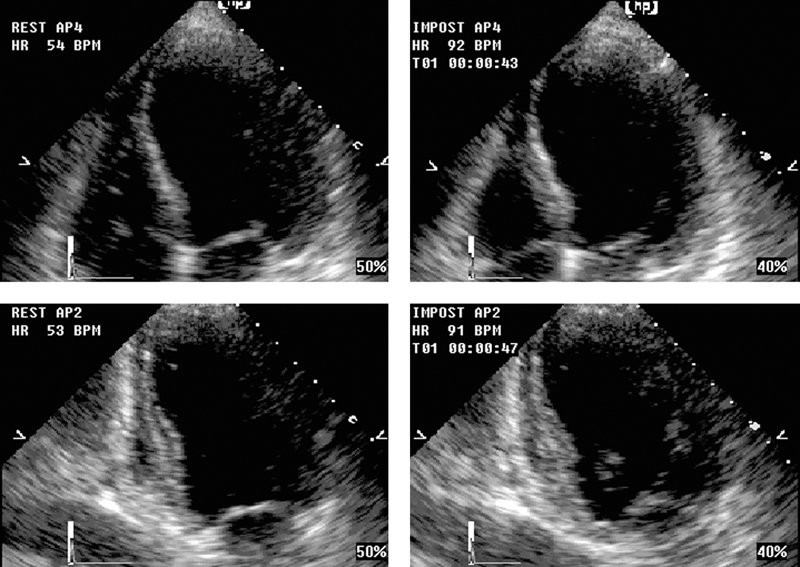

فحوصات تشخيصية لبعض امراض القلب والشرايين التاجية